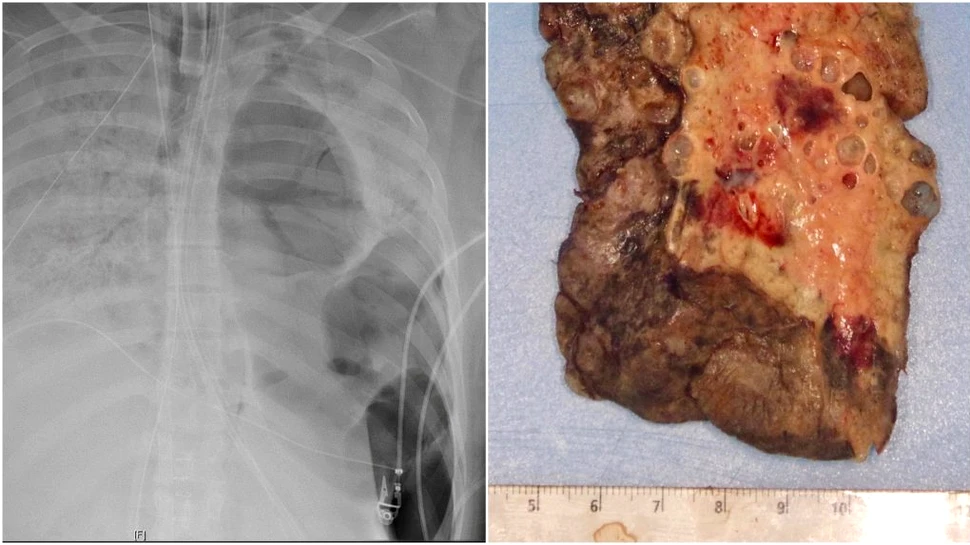

Sursa foto: Northwestern

O pacientă infectată cu COVID-19 a suferit un dublu transplant de plămâni, intervenția chirurgicală fiind o premieră în Statele Unite. Medicii au descoperit că infecția cu noul coronavirus i-a distrus complet plămânii.

Pacienta, care are în jur de 20 de ani, a fost internată timp de șase săptămâni la terapie intensivă în Spitalul Northwestern din Chicago după ce a dezvoltat simptome severe de COVID-19. Tânăra a fost conectată la un ventilator mecanic și un sistem de oxigenare extracorporală (ECMO) pentru ca inima și plămânii săi să poată funcționa în continuare.

Totuși, la începutul lunii iunie, plămânii au prezentat leziuni ireversibile, așa că tânăra a fost pusă pe lista de așteptare pentru un dublu transplant de plămâni. Astfel de intervenții chirurgicale au fost făcute pentru prima oară în anii 1960, dar nu s-au făcut la scară largă până în anii 1990, potrivit Harvard Medical School.

Operația a durat 10 ore, câteva ore mai mult decât normal pentru că inflamația cauzată de COVID-19 a făcut ca plămânii să fie „complet lipiți” de țesutul din jurul lor, de inimă, de peretele toracic și de diafragmă.